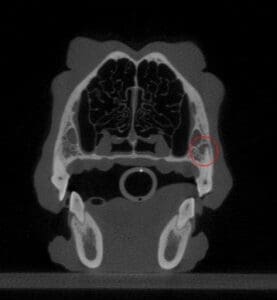

This dog has periapical bone loss at her fractured tooth. This type of bone loss indicates that the pulp has died and resulted in inflammation and/or infection in the surrounding tooth. The dog was eating and behaving like nothing was wrong!